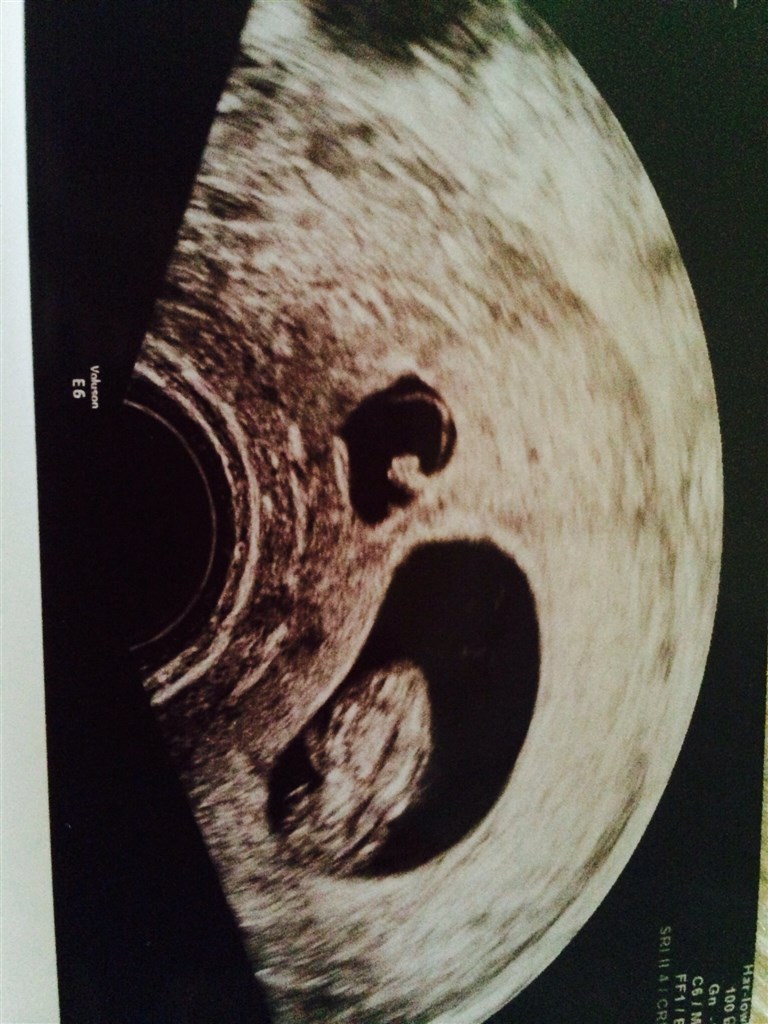

Scanningen idag viste et fint lille foster med arme og ben og et hjerte de slog.

Tvillingen var der dog ikke længere liv i, og den var samme størrelse som sidst.

Men vi er lykkelige for vores lille fis der vokser som den skal og vi er sikre på at det ender med den dejligste lille baby til juni

Billede nr 1 viser størrelses forskellen på de 2 fostre, og nr 2 viser vores lille fis.